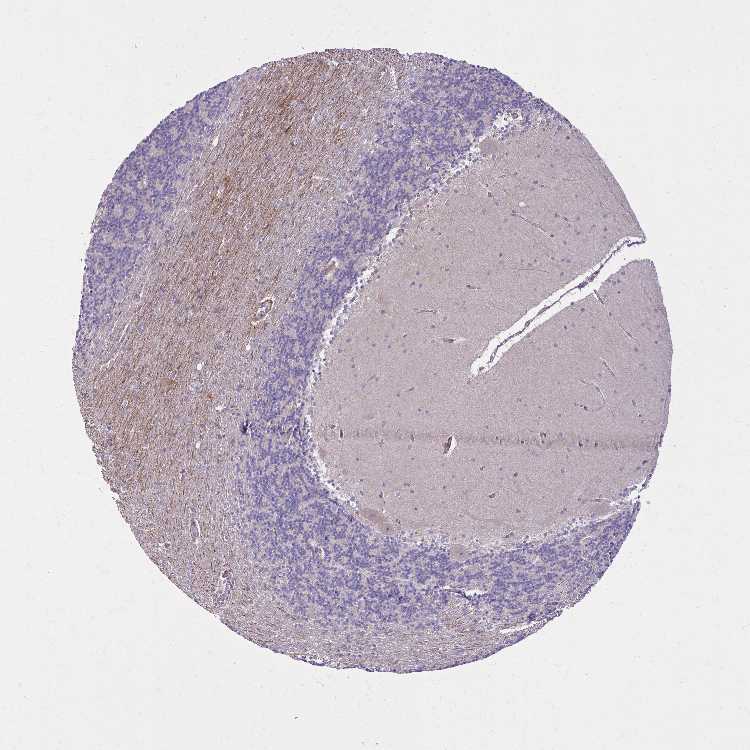

CEREBELLUM - Antibody stainingi

Antibody staining in the annotated cell types in the current human tissue is reported as not detected, low, medium, or high, based on conventional immunohistochemistry profiling in selected tissues. This score is based on the combination of the staining intensity and fraction of stained cells.

Each image is clickable and will lead to virtual microscopy that enables deeper exploration of all samples and also displays staining intensity scores, fraction scores and subcellular localization as well as patient and tissue information for each sample.

Antibody HPA059739

Purkinje cells Medium

Cells in granular layer Not detected

Cells in molecular layer Not detected